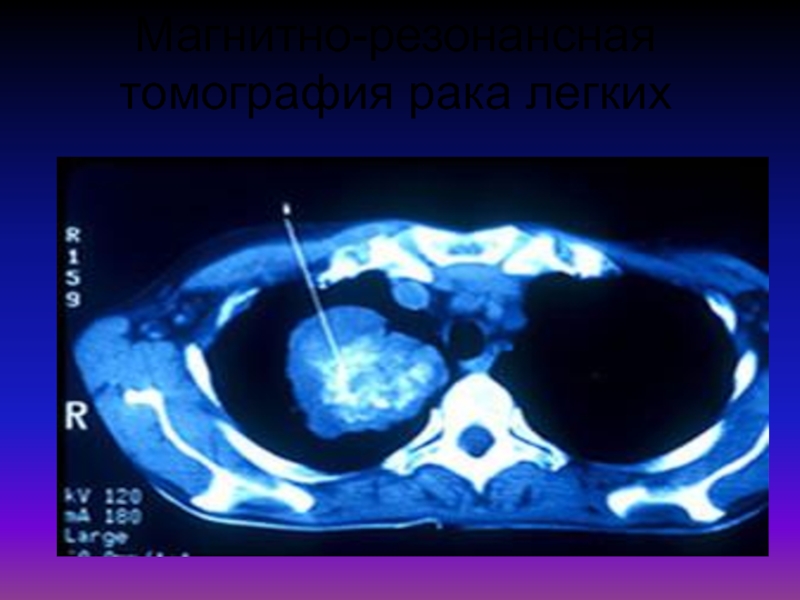

Рентгеновские и МРТ снимки легких